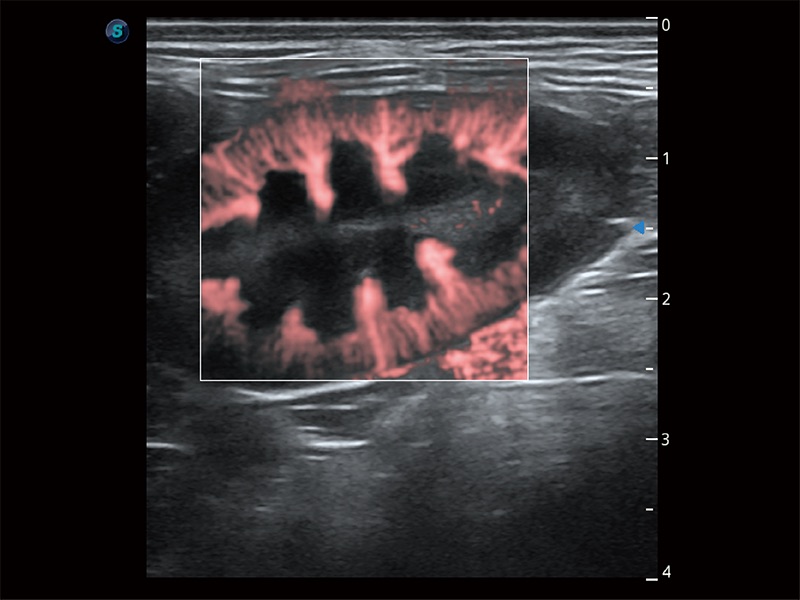

在传统二维血流成像的基础上,呈现血流的立体感,具有动感的生命力之美。即便是微小的血管也能轻松应对,提高了血流的视觉敏感性。

极大提升超低速微细血流的检出能力,同时更精准地滤除软组织和超声信号,为兽用医生提供以往无法通过常规血流获得的疾病诊断信息。